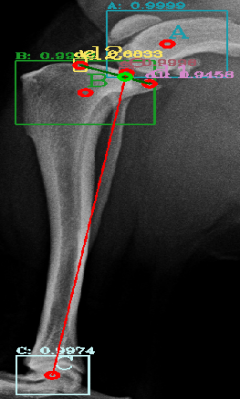

Most of the source dataset of over a thousand unique knee radiographs were distorted, had poor patient positioning, or were otherwise unfit for annotating. 250 of the original images were of sufficient quality to contribute to this effort. These images were set to have 6 different classes for training purposes, as mentioned and shown in Fig. 4. These were then trained using YOLOv3 [10] and the results of the predicted annotations are shown in Table I. From these predictions the centroids were extracted, which is then used to plot the FTL and MTPL. Then using the method mentioned in Section II, TPA is calculated. Examples of images, the region of interests detection and their respective TPA determination is shown in Fig. 6 and Table I:

| Image | YOLOv3 | YOLOv4-1 | YOLOv4-2 | YOLOv4-3 |

|---|---|---|---|---|

| 6(a) | 20.537° | 22.67° | 24.8° | 22.9° |

| 6(b) | 17.354° | 17.62° | 18.7° | 16.22° |

| 6(c) | 19.473° | 19.53° | 20.03° | 18.24° |

| 6(d) | 23.369° | 27.37° | 29.03° | 25.8° |

| 6(e) | 18.435° | 15.5° | 17.65° | 16.8° |

| 6(f) | 19.699° | 18.24° | 20.22° | 18.59° |

For comparison purposes the radiographs have been tested with YOLOv3, original YOLOv4 [12] and custom modifications of the YOLOv4 by changing the activation functions and the results are shown in Table II. The original version of YOLOv4 (addressed as YOLOv4-1 in Table II) combined the Mish, Linear and Leaky activation functions, the versions YOLOv4-2 and YOLOv4-3 used for the purpose of testing in this paper have combinations of Mish, Linear, Swish and Mish, Linear and Relu activation functions respectively. Similarly, comparison of the results that did not fall under the presumed normal range shown in Fig. 9, for the algorithm, are shown with variations in activation function in Table III. It can be seen here that these images, are giving TPA predictions similar to the original YOLOv3, i.e. outside of presumed range.